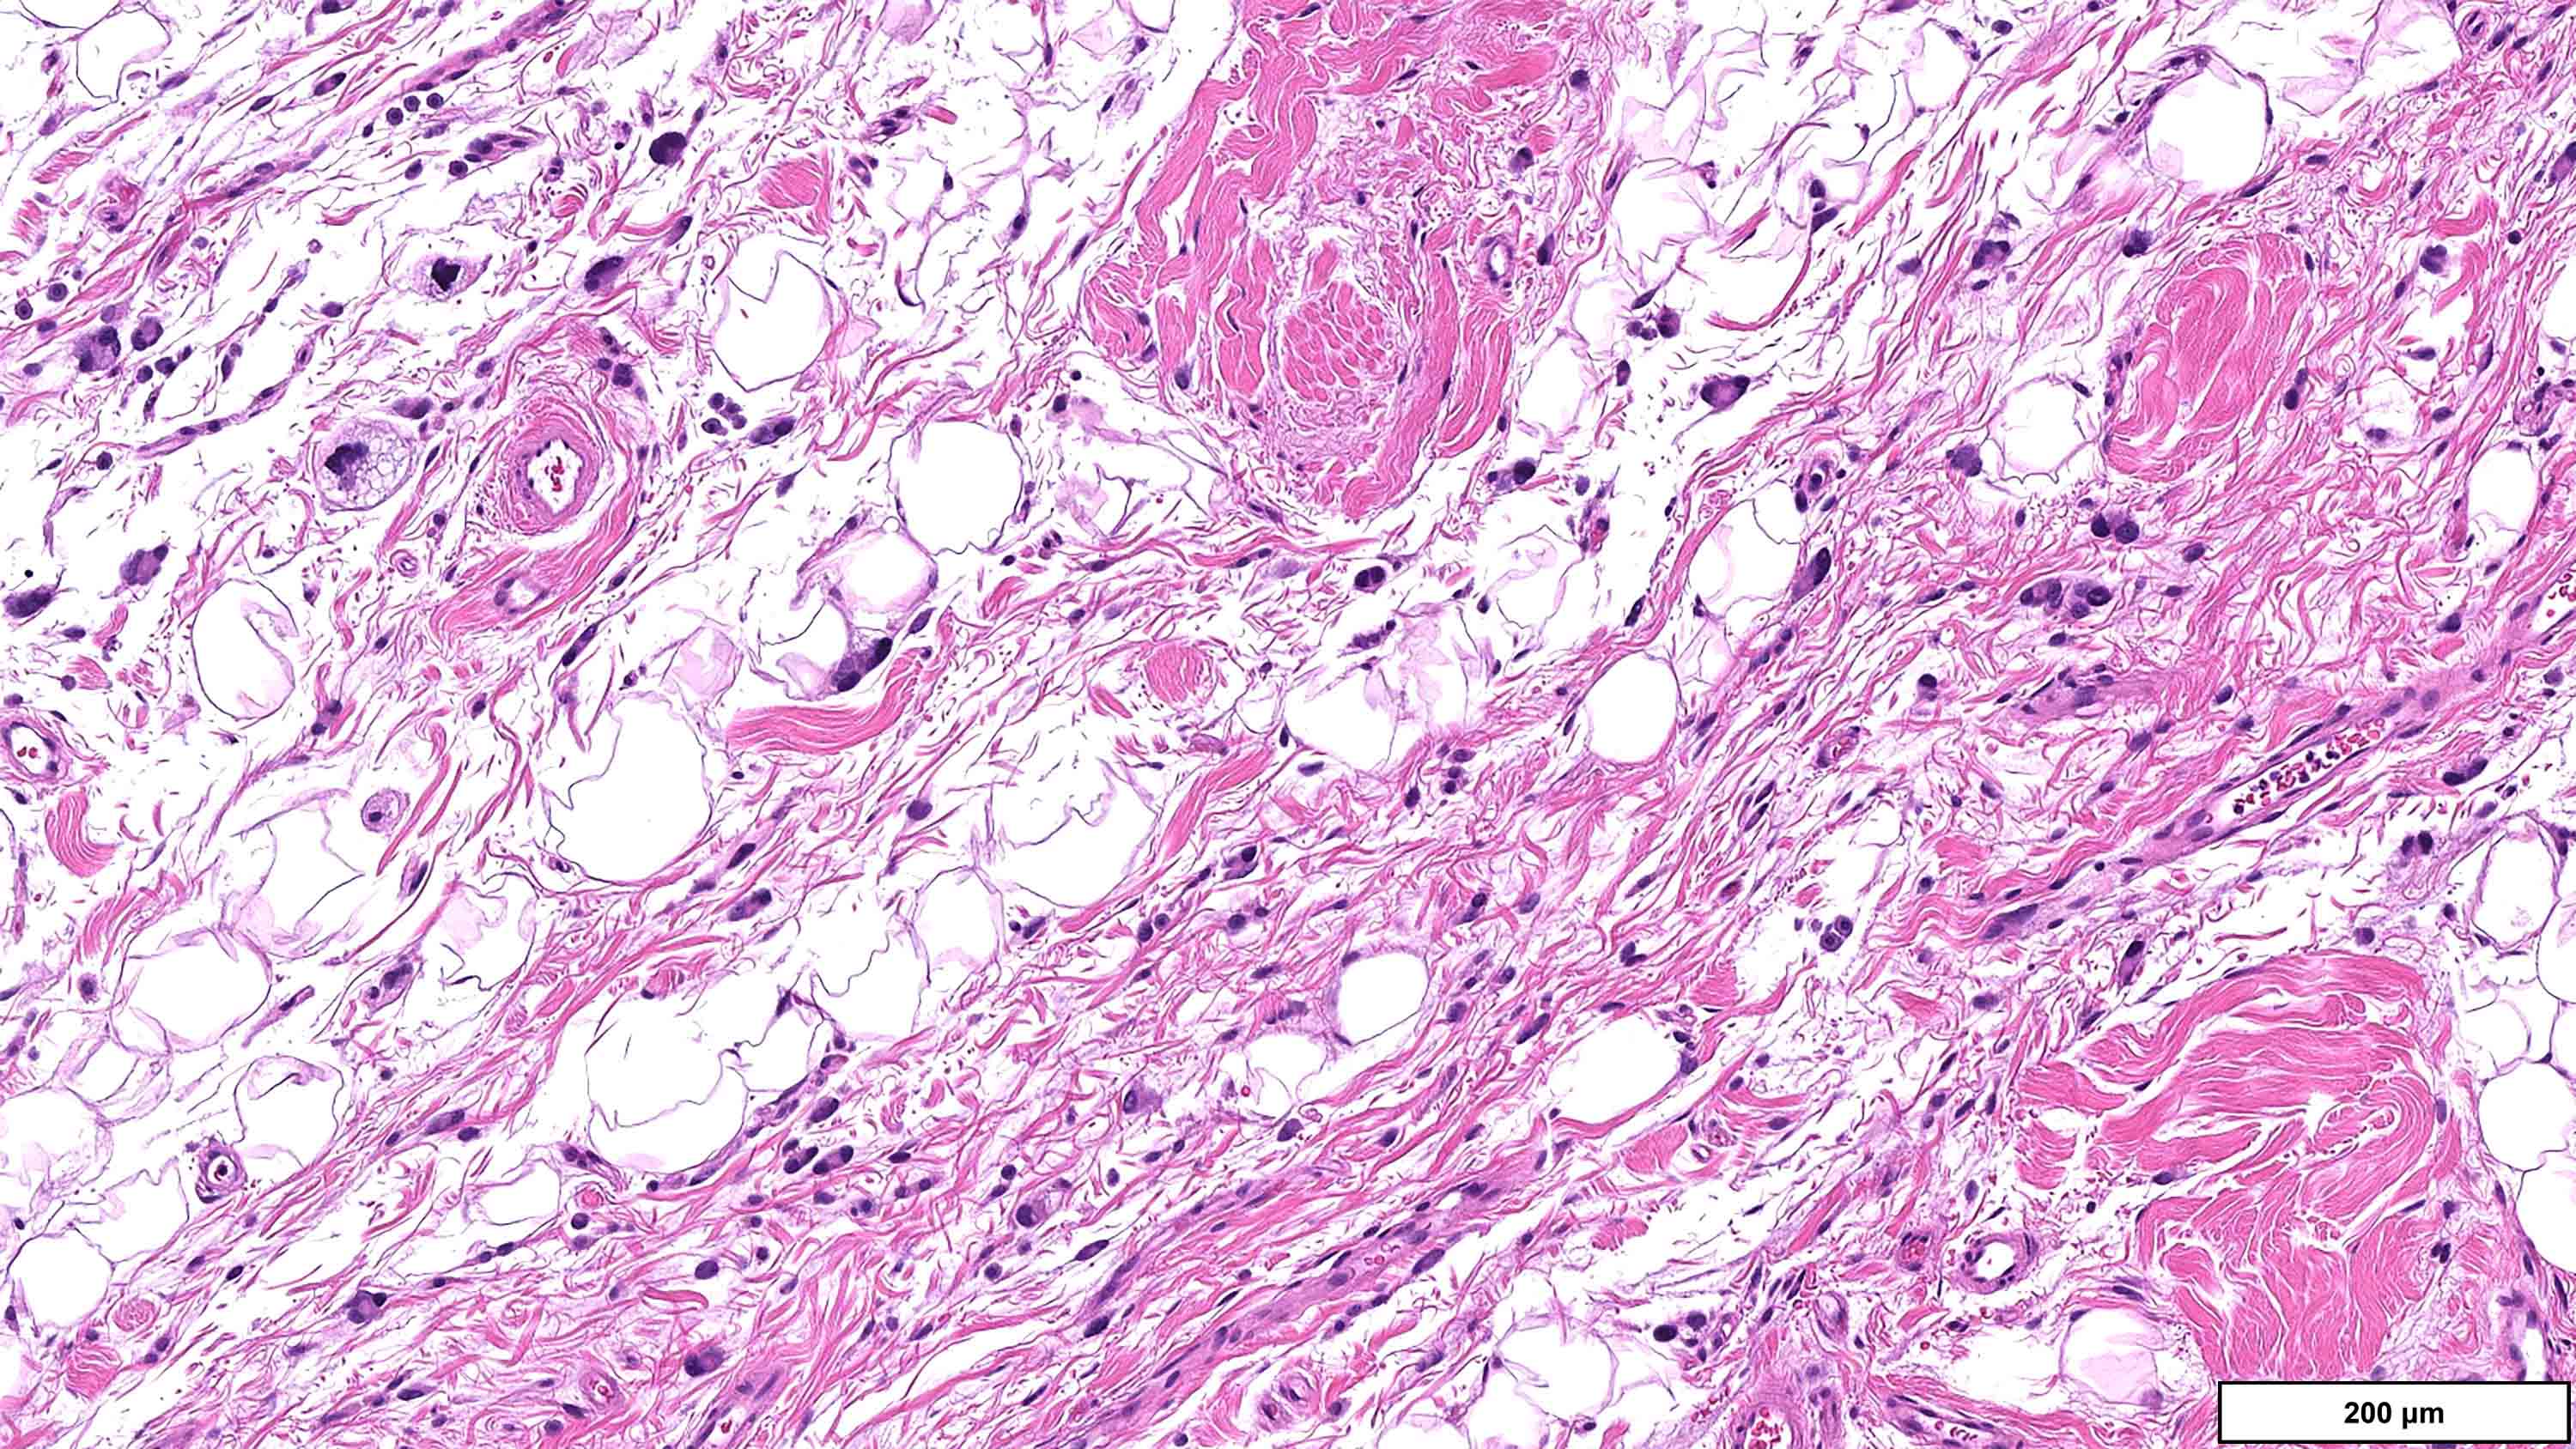

- Sclerosing subtype

- Second most common subtype

- Predilection for retroperitoneal or paratesticular location

- Collagenous fibrous tissue with scattered adipocytes and atypical multinucleated stromal cells

- Scant lipogenic component may be missed in small samples

Microscopic (histologic) images

Contributed by Michael Clay, M.D., Melanie Bourgeau, M.D. and AFIP

Metaplastic change: